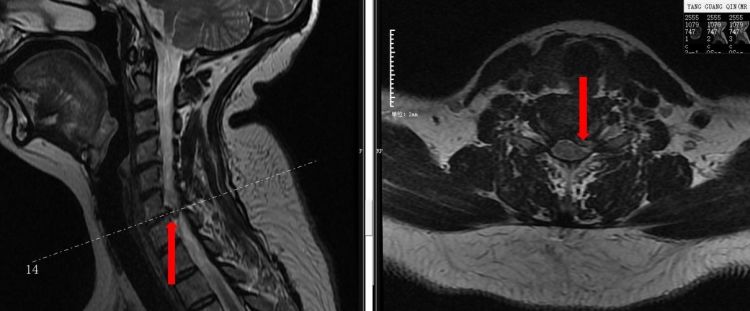

据悉,患者杨某某因“突发颈肩部疼痛伴左上肢放射痛1周”,在当地行非手术治疗4天症状无改善,到我院南顺城医院疼痛科就诊,经诊查后考虑为“神经根型颈椎病”并办理入院治疗。入院后进一步完善患者颈椎X片,CT及颈椎核磁,患者影像学表现与临床表现相符合,进一步明确诊断并拟定手术方案。因颈椎间盘手术风险相对较大,杨经慧主任医师及彭杉刚副主任医师带领团队进行认真术前诊查,术前讨论,排外手术禁忌症,缜密规划手术方案及应急预案。在相关科室的密切配合下开展了左侧C5/6椎间盘脱出伴神经根受压“后路脊柱内镜下椎板减压+椎管成形+椎间盘摘除+神经根粘连松解术”,手术顺利完成。术后第1天,患者因神经根受压导致的左上肢放射痛消除,手术效果明显。